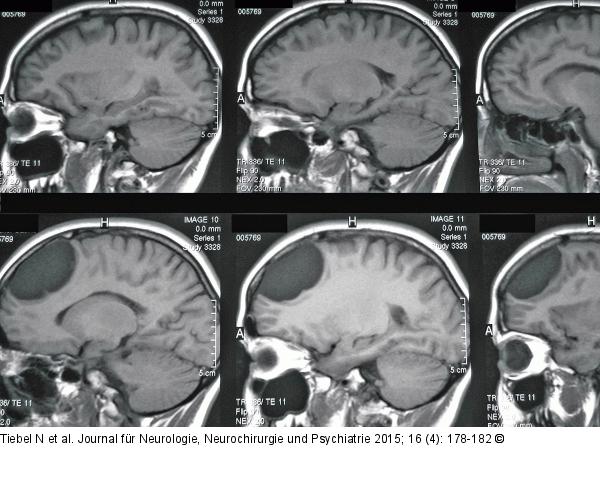

Abbildung 2: Endodermale Zyste Schädel-MRT, T1, sagittal: Die als Arachnoidalzyste diagnostizierte Läsion frontal aus dem Jahr 1999. Damals ein Zufallsbefund im Rahmen einer Burnout-Diagnostik. |

Schädel-MRT, T1, sagittal: Die als Arachnoidalzyste diagnostizierte Läsion frontal aus dem Jahr 1999. Damals ein Zufallsbefund im Rahmen einer Burnout-Diagnostik. |